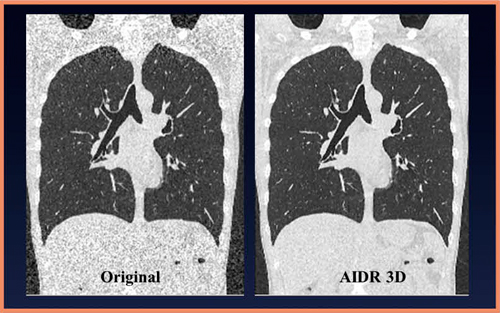

実際の臨床画像での視覚評価について,当大学の大野らが,2012年にAJR誌に発表した論文から1)紹介する。

図3は,70歳代,女性,肺気腫の症例である。基準となる150mAs,AIDR 3D不使用の50mAs,AIDR 3Dを用いた50mAs,同じく25mAsでの不使用と使用の計5画像を比較した。

また,図4は,70歳代,男性のすりガラス状陰影での比較である。図3と同様に150mAsと50mAsのAIDR 3D不使用と使用,25mAsのAIDR 3D不使用と使用の画像である。図5は,60歳代,女性の肺間質性病変で,図3,4と同様の条件で撮影している。

これら3症例を含めた画質の評価については,AIDR 3Dを用いた低線量での撮影画像が,150mAsの基準画像と比べて遜色がなかったと報告されている。このようにファントム実験と臨床画像のいずれからも,低線量撮影でのAIDR 3Dの有用性がわかる。